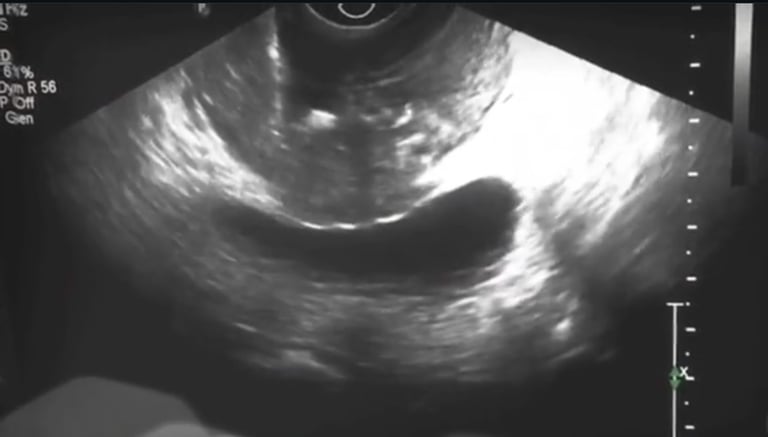

Transrektal Yöntem: En sık kullanılan yöntemdir. Ultrason probu rektuma yerleştirilir ve biyopsi iğnesiyle prostat dokusundan örnek alınır.